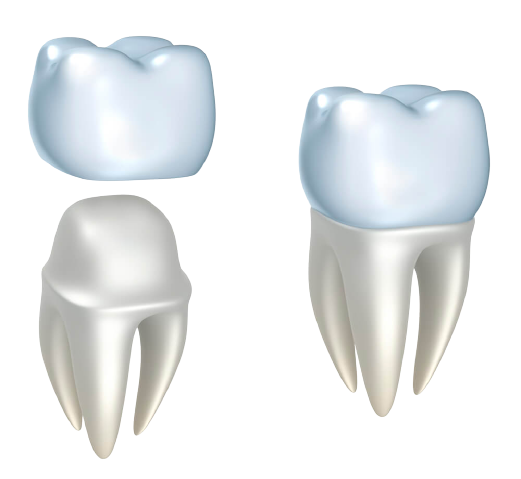

Total oral rehabilitation with implantation and crowns

Total oral rehabilitation with implantation and crowns